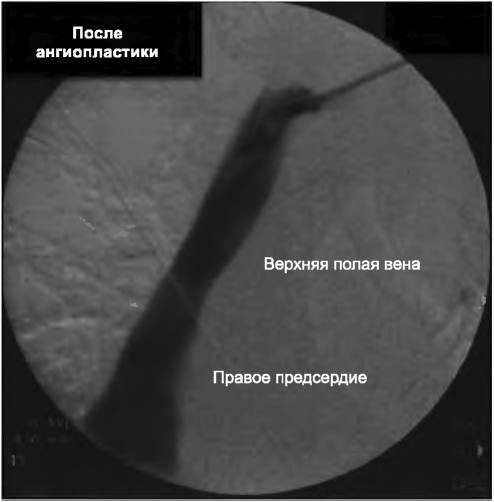

А. Начальная дисфункция. Недавно установленные катетеры могут давать плохой кровоток из-за перегиба, сдавления катетера внутри туннеля отеком, неправильного положения катетера (в непарной или полунепарной вене) или неправильного расположения кончика катетера (рис. 9.3). Для диагностики полезна рентгенография. Отек в туннеле обычно разрешается за 24 часа. Наличие перегиба или неправильного расположения кончика катетера требует его перестановки с созданием другого туннеля или использования другой длины катетера. Важно также устанавливать катетер в нижней части шеи близко к ключице; высокое расположение катетера на шее может сделать катетер «позиционным», с кровотоком, зависящим от положения шеи. Фактически кончик катетера поднимается при наклоне шеи, приводя к плохому кровотоку. Место выхода близко к молочной железе может также тянуть кончик катетера вверх, в верхнюю полую вену. Экструзия муфты в результате перемещения катетера или эрозия тканей повышают риски дисфункции и инфекции. Такие катетеры требуют замены.

РИСУНОК 9.3. Перегиб: катетер в левой яремной вене с перегибом

Если в туннеле есть эрозия или он инфицирован, требуется создание нового туннеля или новое место установки. Катетеры в левой яремной вене характеризуются большей частотой дисфункции, чем в правой (Engstrom, 2013), по не вполне понятным причинам, возможно, из-за извилистого пути до входа в правое предсердие.